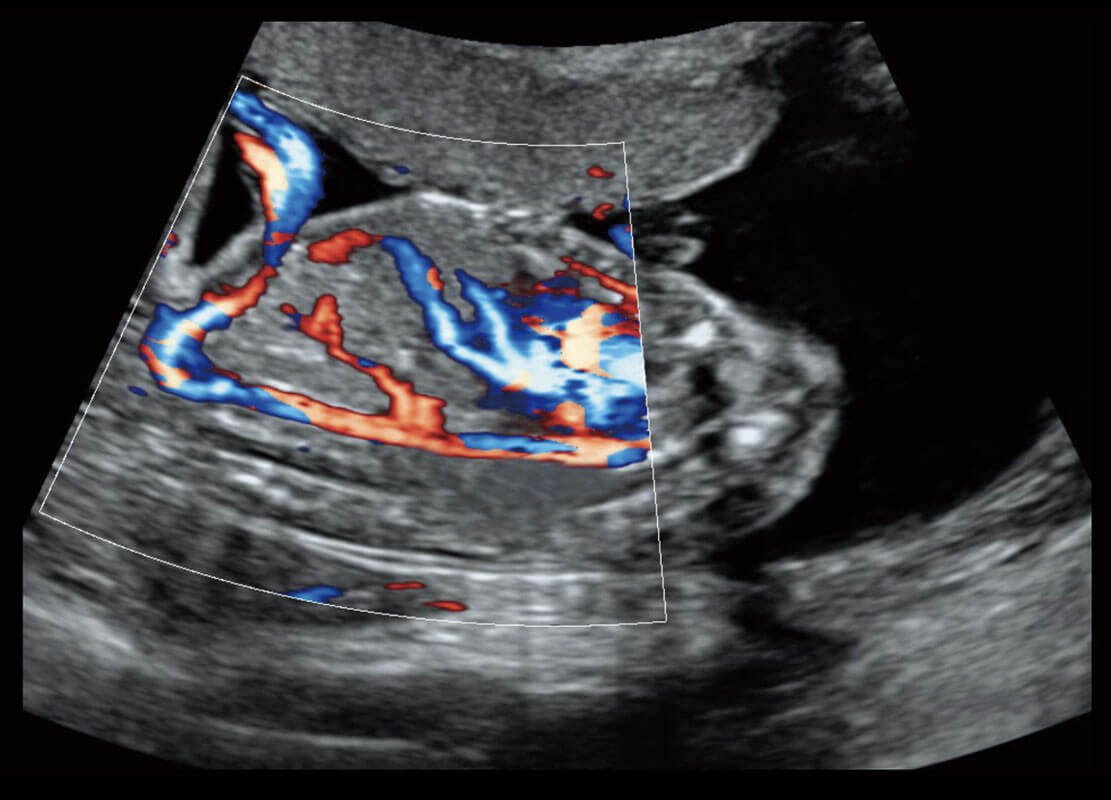

盆底超声

P60为盆底超声检查提供应用方案,多种腔内及腹部容积探头提供从二维、三维到四维的优异图像品质,实时快速三维容积数据获取,专业的测量工具包等人性化设计,为超声医生诊断提供有力保障。

Lev.Hiat A-r: 16.33 cm2

Lev.Hiat H-r: 53.70 mm

Lev.Hiat W-r: 43.96 mm

Lt-LUG-r: 24.16 mm

Rt-LUG-r: 19.94 mm

S-Pelvic

能够简化盆底检查的操作流程,可在二维模式及三维成像模式下实现一键自动提取出标准切面、自动识别当前切面、自动测量,提升盆底检查的高效性,同时也能让青年医生快捷的获得准确的检查结果。